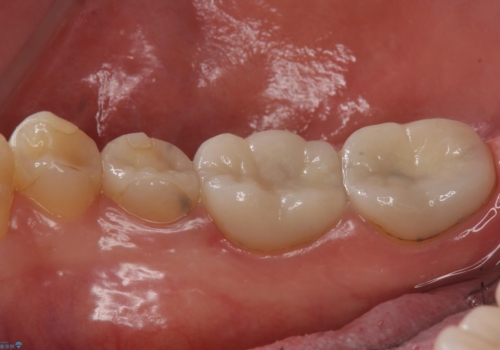

樹脂で継ぎ接ぎになった歯 セラミッククラウンでの治療

- 樹脂の材料の着色が気になるとのことで来院されました。

継ぎ接ぎになっている部分が多かったためクラウンでの治療となりました。

樹脂の材料と歯の境界部分は虫歯・着色の好発部位となります。

度重なる治療で継ぎ接ぎになってしまった場合はクラウンで歯を覆った方が虫歯・着色のリスクを減らすことができます。